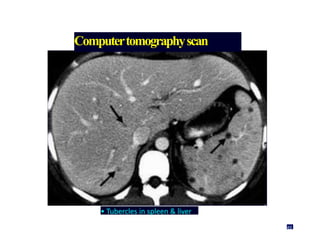

Computertomographyscan

Enlarged paraaortic LN

48

• Tubercles in spleen & liver